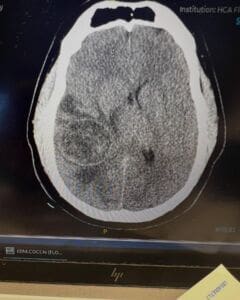

Corey Brooks, a well-known youth coach with the city of Mount Dora, was recently taken to the emergency room with an intense headache. A CT scan revealed a 4.8-by-4.3 centimeter mass in his brain, which had caused a 6mm midline shift — a serious neurological concern that prompted immediate action.